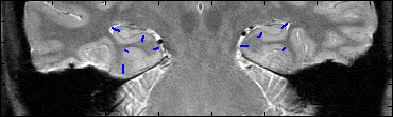

This is an example of one subjects demarcation. The A/P slice is slice

3.